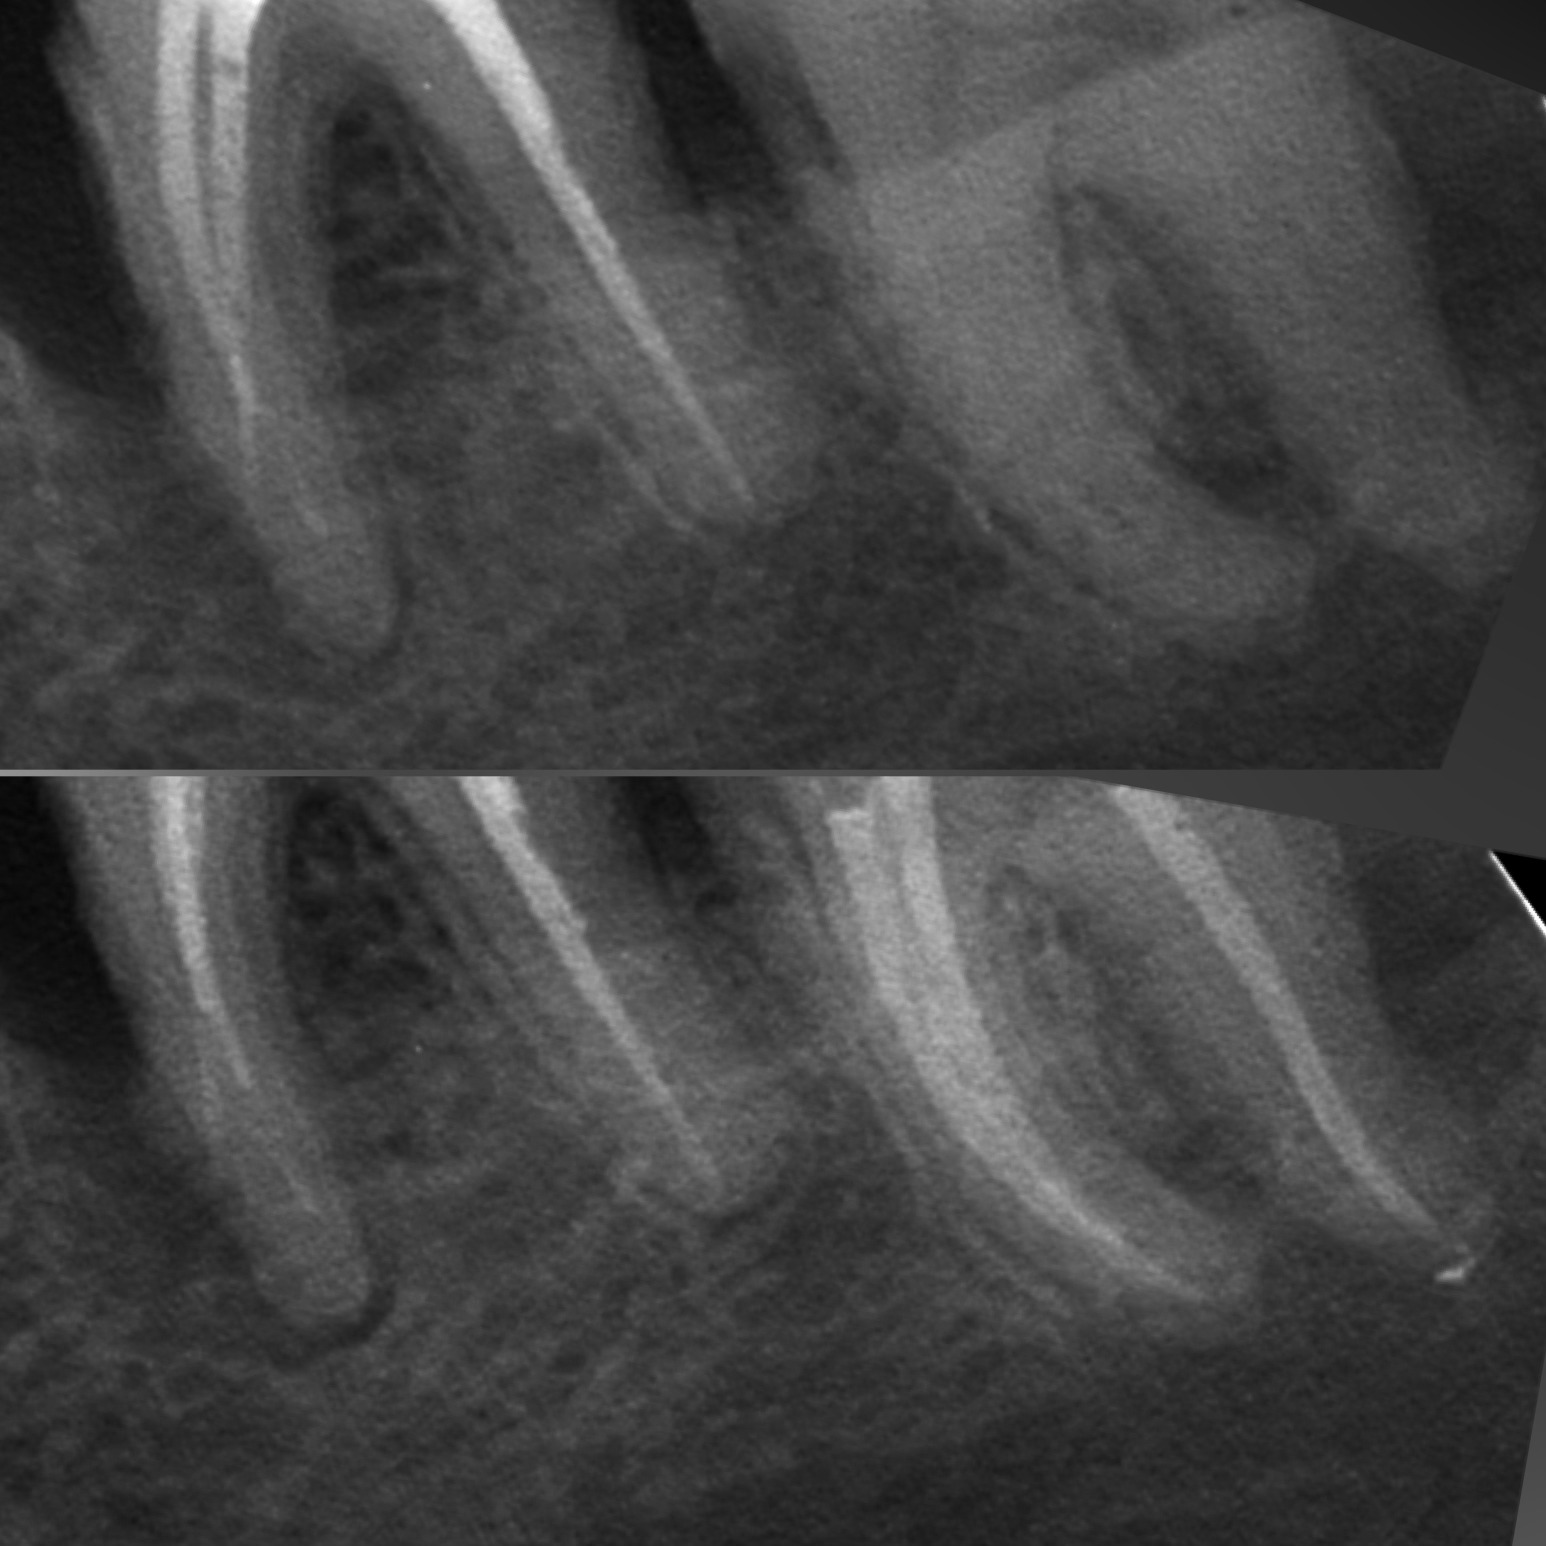

• Диагностика и лечение кариеса и его осложнений (пульпиты, периодонтиты)

• Эндодонтическое лечение корневых каналов с использованием стоматологического микроскопа